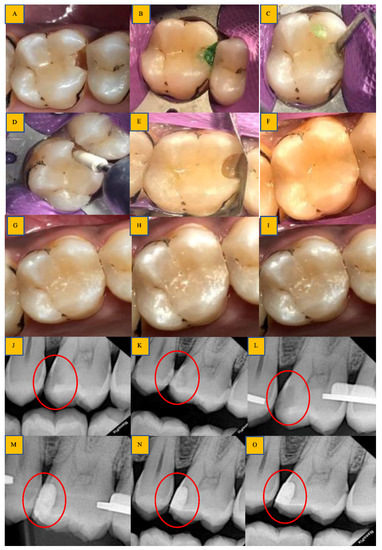

توضیحاتدای آشکار ساز پوسیدگی کبالت cobaltمحلول تشخیص پوسیدگی لایه ی سطحی از عاج پوسیده را رنگ کرده و از لایه ی زیرین عاج سالم و یا پوسیده متمایز میکند . این رنگ پذیری لایه ای باعث برداشت حداقلی از عاج پوسیده شده و به عنوان یک راهنمای مفید در برداشت پوسیدگی عمل میکند .این محصول فقط برای کاربرد دندانی طراحی شده استهنگام مصرف از دستکش استفاده شود و برای جلوگیری از واکنش حساسیت زایی از تماس مستقیم با دست جلوگیری کنیدپس از کار با محصول درب آن را ببندیدو از ورود رطوبت به بطری پیشگیری کنیدCobalt Caries Detector Dye – نشانگر پوسیدگی کبالتپوسیدگیهای دندانی در تمامی شکافها و منافذ سطح دندان جای میگیرند. به همین دلیل تشخیص دقیق محل پوسیدگیها روی سطح دندان کار بسیار مشکلی است. گاهی اوقات ممکن است دندانپزشک از آینه دندانپزشکی برای مشاهدۀ پوسیدگیهایی که درون کانالهای دندانی قرار دارند استفاده کند. اما برخی از پوسیدگیها به حدی جزئی هستند که نمیتوان همه آنها را با چشم مسلح تشخیص داد.در این حالت باید از محصولی به نام نشانگر پوسیدگی استفاده کرد.نشانگر پوسیدگی کبالتیکی از بهترین محصولاتی است که در این زمینه به دندانپزشکان پیشنهاد میشود. آماده کردن این نشانگر پوسیدگی بسیار راحت است و به همین دلیل باعث هدر رفتن وقت دندانپزشک نخواهد شد. به کمک این محصول میتوان تمامی بخشهای دندان که مشاهدۀ پوسیدگی روی سطح آنها دشوار است را مشاهده کرد.ویژگی های نشانگر پوسیدگی دندان کبالتاین نشانگر مقدار دقیق و جزئی پوسیدگیها را نشان میدهد. در نتیجه از برداشتن بیش از حد بخشهای داخلی کانال دندان جلوگیری خواهد کرد.نشانگر پوسیدگی کبالت در مواجهه با پوسیدگیها تغییر رنگ میدهد.بسته بندی نشانگر پوسیدگی کبالت شامل 6 میل مایع و یک عدد سرنگ است.نشانگر پوسیدگی دندان کبالتهمچنین از بروز خطای چشم جلوگیری میکند و یک محصول کاملاً متمایز و عالی برای مشاهدۀ پوسیدگیهای دندانی است.